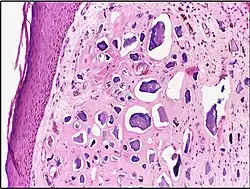

Calcinosis cutis Calcinosis cutis in human tissue

Calcinosis cutis in human tissue